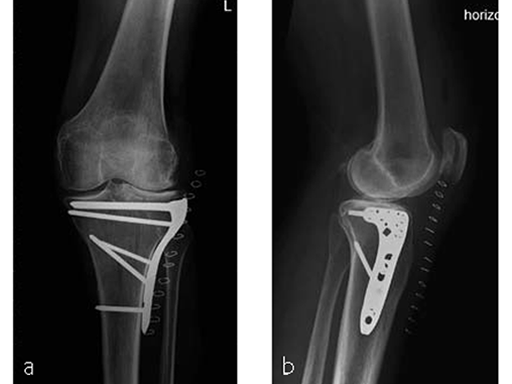

Case provided by Christian Ryf, Davos, Switzerland

Case: Hiking accident

A 70-year-old female patient had an accident while hiking. Osteoporosis was preexisting but with asymptomatic moderate degenerative osteoarthritis of the knee with chondrocalcinosis of the lateral compartment (Fig 1 and 2).

The area was functional soon after treatment (Fig 3), and the patient was able to experience weight bearing of 20 kg for the first 6 weeks. She was completely pain free after 6 weeks (Fig 4) with excellent muscular function and coordination, therefore unlimited weight bearing after the first follow-up was enabled.